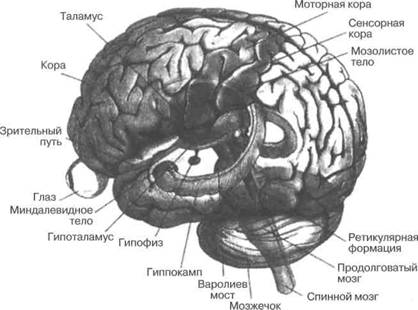

И какие же именно структурные улучшения мозга были ключевыми для всего этого? Буду счастлив объяснить. Но прежде чем начать, я дам вам краткий обзор анатомии головного мозга, чтобы вы смогли лучше понять ответ.

Краткая экскурсия по вашему мозгу

Человеческий мозг состоит из примерно 100 миллиардов нервных клеток, или нейронов (см. рис. В.1). Нейроны «общаются» друг с другом благодаря нитеобразным волокнам, которые напоминают либо густые ветвистые заросли (дендриты), либо длинные извилистые передаточные кабели (аксоны). Каждый нейрон создает от ста до десяти тысяч связей с другими нейронами. Точки контакта

Человеческий мозг похож на грецкий орех, разделенный на две зеркально похожие половины (см. рис. В.2). Эти раковинообразные половинки являются мозговой корой. Кора разделена посередине на две полушария, левое и правое. У людей кора столь сильно разрослась, что вынуждена была принять складчатую, извилистую форму, дав мозгу его знаменитую внешность, напоминающую цветную капусту. (А вот у большинства млекопитающих кора ровная и гладкая, в лучшем случае с несколькими извилинами на поверхности.) По

Рис. В.2. Человеческий мозг, вид сверху и слева. Верхний рисунок показывает два зеркально-симметричных полушария, каждое из которых контролирует движения противоположной части тела и получает от нее сигналы (хотя из этого правила есть исключения). Сокращения: ДПК - дорсолатеральная префронтальная кора; ОФК - орбитофронтальная кора; НТД - нижняя теменная долька; О - островок, спрятанный глубоко под Сильвиевой бороздой ниже лобной доли. Вентромедиальная префронтальная кора (ВПК, не обозначено) спрятана во внутренней нижней части лобной доли, и ОФК является ее частью

Рис. В.З. Схематичное изображение человеческого мозга, показаны внутренние структуры: миндалевидное тело, гиппокамп, базальные ганглии и гипоталамус

существу дела, кора — месторасположение высшей мыслительной деятельности, та самая tabula rasa (хотя это далеко не так), где осуществляются высшие интеллектуальные функции. Неудивительно, что она особенно хорошо развита у двух видов млекопитающих — дельфинов и приматов. Несколько позже мы еще вернемся к коре. А сейчас посмотрим на другие части мозга.

Сквозь всю сердцевину позвоночного столба проходит толстый пучок нервных волокон — спинной мозг, который обеспечивает постоянный поток сообщений между мозгом и телом. Эти сообщения включают в себя, например, информацию о прикосновениях и боли, приходящую от кожи, и двигательные команды, «стучащие в дверь» к мышцам. В самой верхней части спинной мозг выходит из своей костной оболочки из позвонков, входит в череп и становится толстым и похожим на луковицу (см. рис. В.З). Это утолщение называется стволовой частью мозга и разделяется на три доли: продолговатый мозг, варолиев мост и средний мозг. Продолговатый мозг и ядра (группы нейронов) на основании варолиева моста контролируют важные жизненные функции, такие как дыхание, кровяное давление и температура тела. Кровотечение даже из малейшей артерии, снабжающей этот район, может повлечь за собой немедленную смерть. Как это ни парадоксально, высшие области мозга могут вынести сравнительно обширное повреждение, и пациент при этом останется жив и даже будет находиться в хорошей физической форме. Например, обширная опухоль в лобной доле может вызвать почти незаметные неврологические симптомы.

На верхней стенке варолиева моста располагается мозжечок (лат. cerebellum, буквально «маленький мозг»), контролирующий правильную координацию движений, а также вовлеченный в управление равновесием, походкой и положением тела. Когда двигательная зона коры вашего головного мозга (высшая мозговая область, отдающая сознательные двигательные команды) посылает сигнал мышцам через спинной мозг, копия этого сигнала — нечто вроде электронного письма от управляющего делами — посылается в мозжечок. Мозжечок также получает сенсорный отклик от мышцы и проприорецеп-торов по всему телу. Благодаря этому мозжечок способен определить любые несовпадения, образующиеся между планируемым и реальным действием, и в ответ может внести соответствующие поправки в исходящий двигательный сигнал. Такой вид механизма, управляемого в реальном времени с помощью обратной связи, называется следящей системой управления, или сервоуправляемой системой. Повреждения мозжечка делают систему неустойчивой. Например, пациентка пытается дотронуться до своего носа, чувствует, что рука промахнулась, и пытается компенсировать это движением в противоположную сторону, что заставляет ее руку промахнуться еще больше, только в противоположном направлении. Это называется динамическим дрожанием, или тремором.

Верхнюю часть ствола мозга окружают таламус (зрительный бугор) и базальные ядра. Таламус получает основную входящую информацию от органов чувств и пересылает ее в чувствительную часть коры мозга для более сложной обработки. Зачем нам нужна передаточная станция, пока еще не совсем ясно. Базальные ядра — это имеющая странную форму группа образований, которые имеют отношение к контролю над автоматическими движениями, связанными со сложными сознательными действиями, например, регулирующие положение плеча при броске дротика, или координирующие силу и напряжение во множестве мышц вашего тела во время ходьбы. Повреждение клеток в базальных ядрах проявляется в таких расстройствах, как болезнь Паркинсона, при которой туловище пациента малоподвижно, его лицо представляет собой бесчувственную маску, а сам он ходит характерной шаркающей походкой. (Наш профессор неврологии в медицинском университете обычно диагностировал болезнь Паркинсона, просто прислушиваясь к раздающимся поблизости шагам пациента; если мы не могли проделать то же самое, он нас заваливал. То было время предшествующее эпохе высокотехнологичной медицины и магнитно-резонансной томографии, или МРТ.) Напротив, избыточное количество мозгового химического вещества допамина в базальных ядрах может привести к расстройству, известному как хорея, характеризующемуся неконтролируемыми движениями, имеющими внешнее сходство с танцем.

Наконец мы переходим к коре головного мозга. Каждое полушарие головного мозга подразделяется на четыре доли (см. рис. В.2): затылочную, височную, теменную и лобную. У каждой из этих долей свои определенные сферы функционирования, хотя на практике уровень их взаимодействия очень высок.